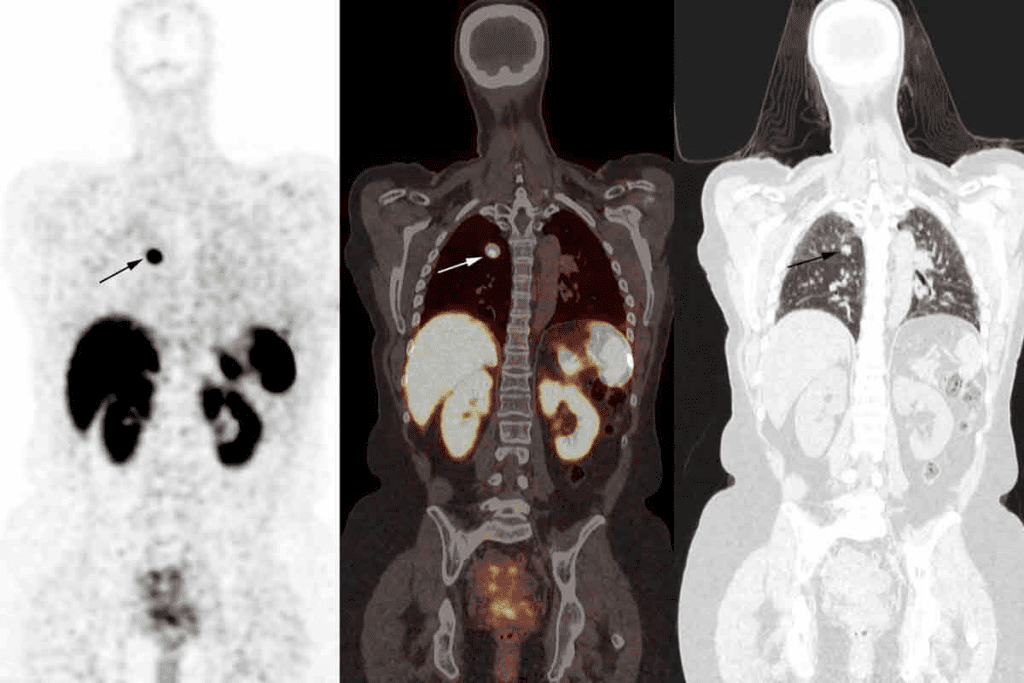

Metastatic Cancer to Bones

Metastatic cancer to bones is more common and occurs when cancer cells from other parts of the body, such as the breast, prostate, or lung, spread to the bone. Bone scans are particularly useful in detecting metastatic bone disease, as they can show areas of increased uptake corresponding to metastatic deposits.

Characteristic Patterns of Cancerous Uptake

Cancerous uptake on bone scans often exhibits characteristic patterns that help in diagnosis. For instance, metastatic disease can cause multiple areas of increased uptake scattered throughout the skeleton. In contrast, primary bone tumors may show a more localized area of uptake. Understanding these patterns is crucial for interpreting bone scan results accurately.

The information from bone scans, combined with clinical history and other diagnostic tests, enables healthcare providers to diagnose and monitor cancer effectively. By recognizing the characteristic patterns of cancerous uptake, doctors can make informed decisions about treatment and follow-up care.